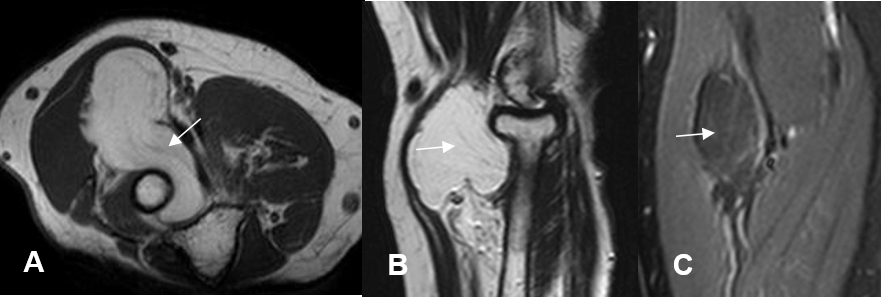

Fig 55. Compresión mediano.

A: RM axial en T1, B: RM sagiltal en T2 y C: RM coronal en STIR. Imagen lobulada que sigue la señal de la grasa y corresponde a lipoma. Rodea el tercio proximal del radio y desplaza el nervio mediano.